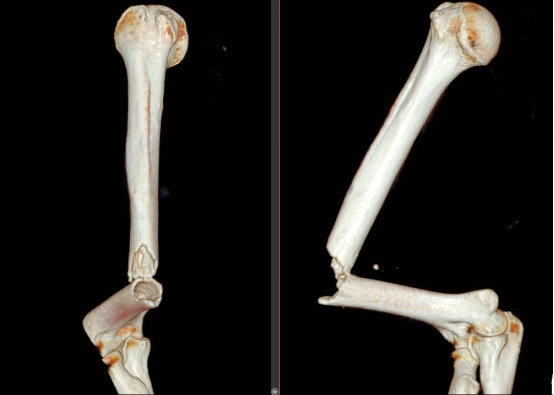

术前三维重建

患者为90岁男性,因不慎摔倒导致右肱骨骨折,被紧急送往医院,收入脊柱创伤外科。骨折的治疗本身就充满挑战更凶险的是老人的全身基础状况。术前检查显示,患者血糖控制极差,且冠脉CTA提示存在冠脉重度狭窄。这意味着,在麻醉和手术过程中,患者心脏随时可能出现意外,手术风险堪称“高危中的高危”。